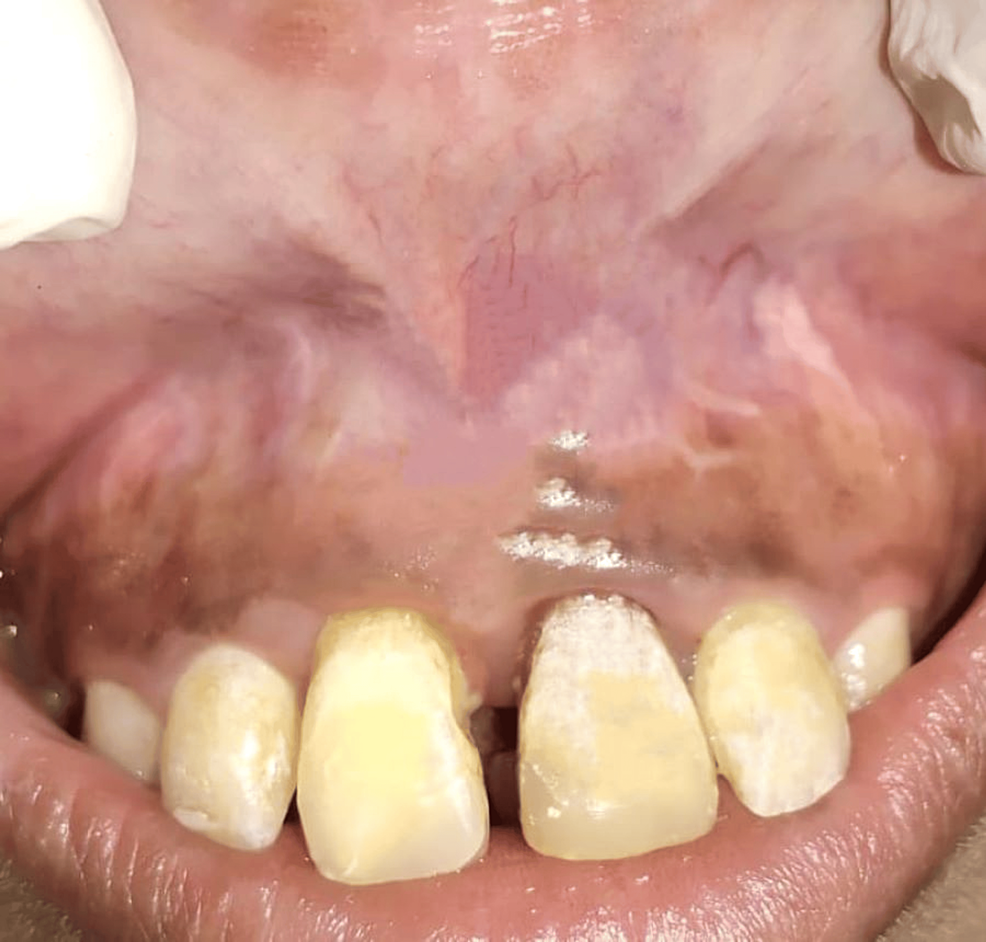

Figure 1 from Using the diode laser in the lower labial frenum removal

Figure 1 from Using the diode laser in the lower labial frenum removal Diode Laser Labial Frenectomy It also demonstrates the finest possible outcome potential for minimally invasive dentistry. After completion of fixed orthodontic treatment and primary closure of maxillary diastema, the patients were randomly assigned into three. Diode laser frenectomy is a safe and effective approach for treating. The use of diode laser frenectomy without infiltrated anesthesia is currently a novel technique. An abnormal labial frenum. Diode Laser Labial Frenectomy.